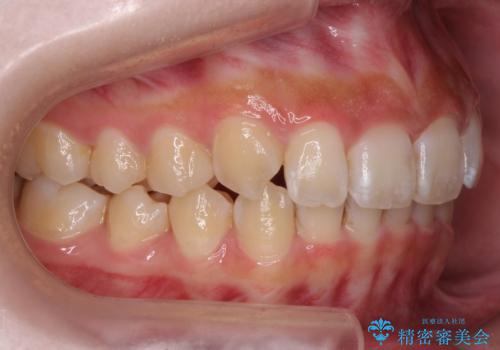

前歯の並び インビザライン 非抜歯で 深いかみ合わせの治療

- 前歯の並びを気にして来院。

上の前歯が内側に倒れこんでいました。

インビザラインで前歯の並びを整えています。

前歯の重なりが大きいいわゆる過蓋咬合を呈していましたが、ある程度適正な重なりにすることができました。